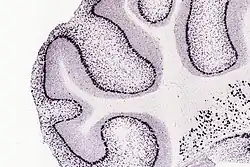

Parvalbumin (PV) je přítomen v GABAergických interneuronech v nervovém systému, zejména v retikulárním thalamu, [4] a je exprimován převážně tzv. "lustrovými" (chandeler) a košovými (basket) buňkami v kůře. V mozečku je PV exprimován v Purkyňových buňkách a interneuronech molekulární vrstvy. [5] V hippocampu jsou interneurony PV rozděleny do košových, axo-axonických, bistratických a oriens-lacunosum moleculare (O-LM) buněk, přičemž každý podtyp je zaměřen na odlišné domény pyramidálních buněk . [6]